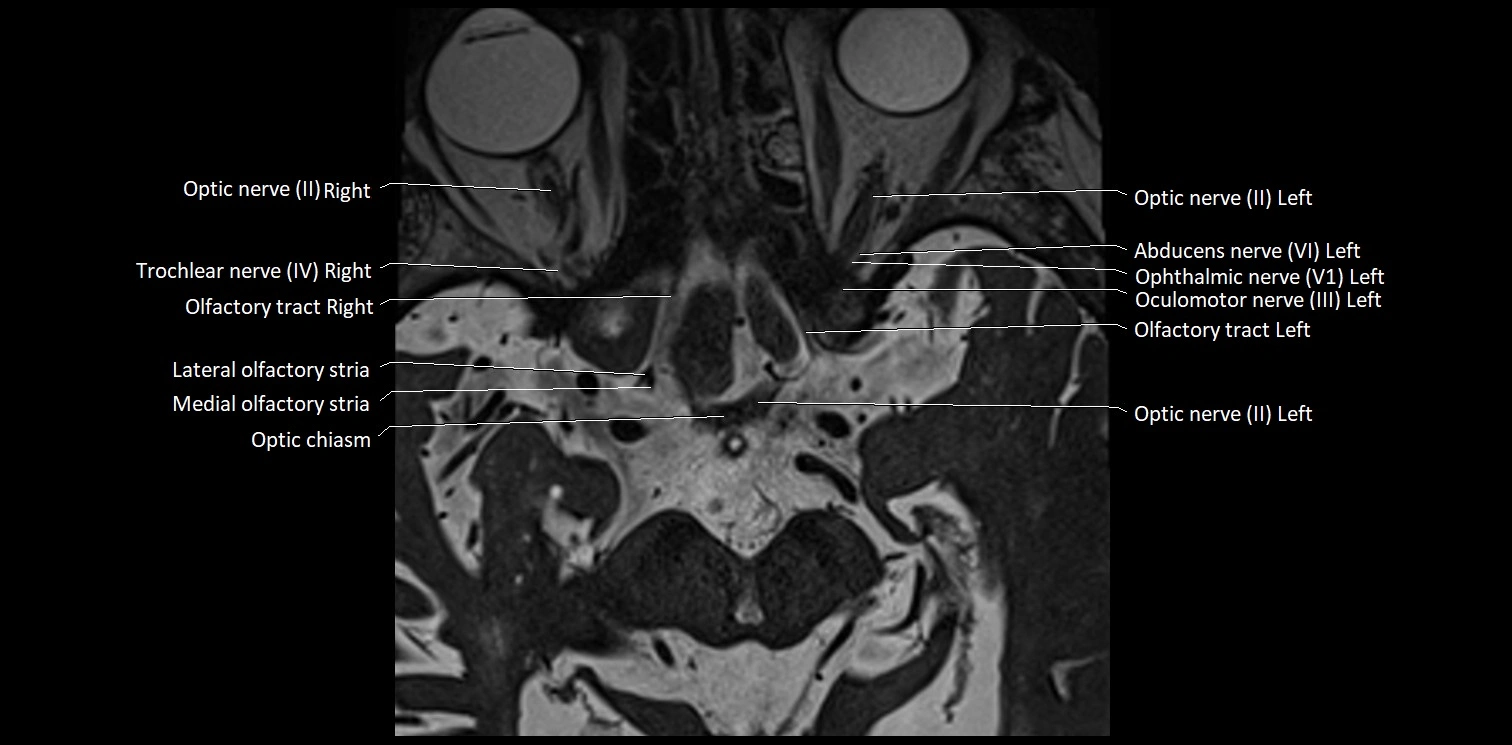

MRI Appearance

• The abducens nerve is a small, thin, linear structure

• Best visualized on high-resolution T2-weighted 3D MRI sequences (e.g., FIESTA or CISS)

• Seen as a hypointense (dark) line running from the brainstem at the pontomedullary junction, traversing the prepontine cistern, and entering Dorello’s canal under the petrosphenoidal ligament, then into the cavernous sinus, and finally the orbit

• May be challenging to visualize in standard MRI due to its small size

• Pathology may be inferred by absence, displacement, or enhancement of the nerve

MRI images

image